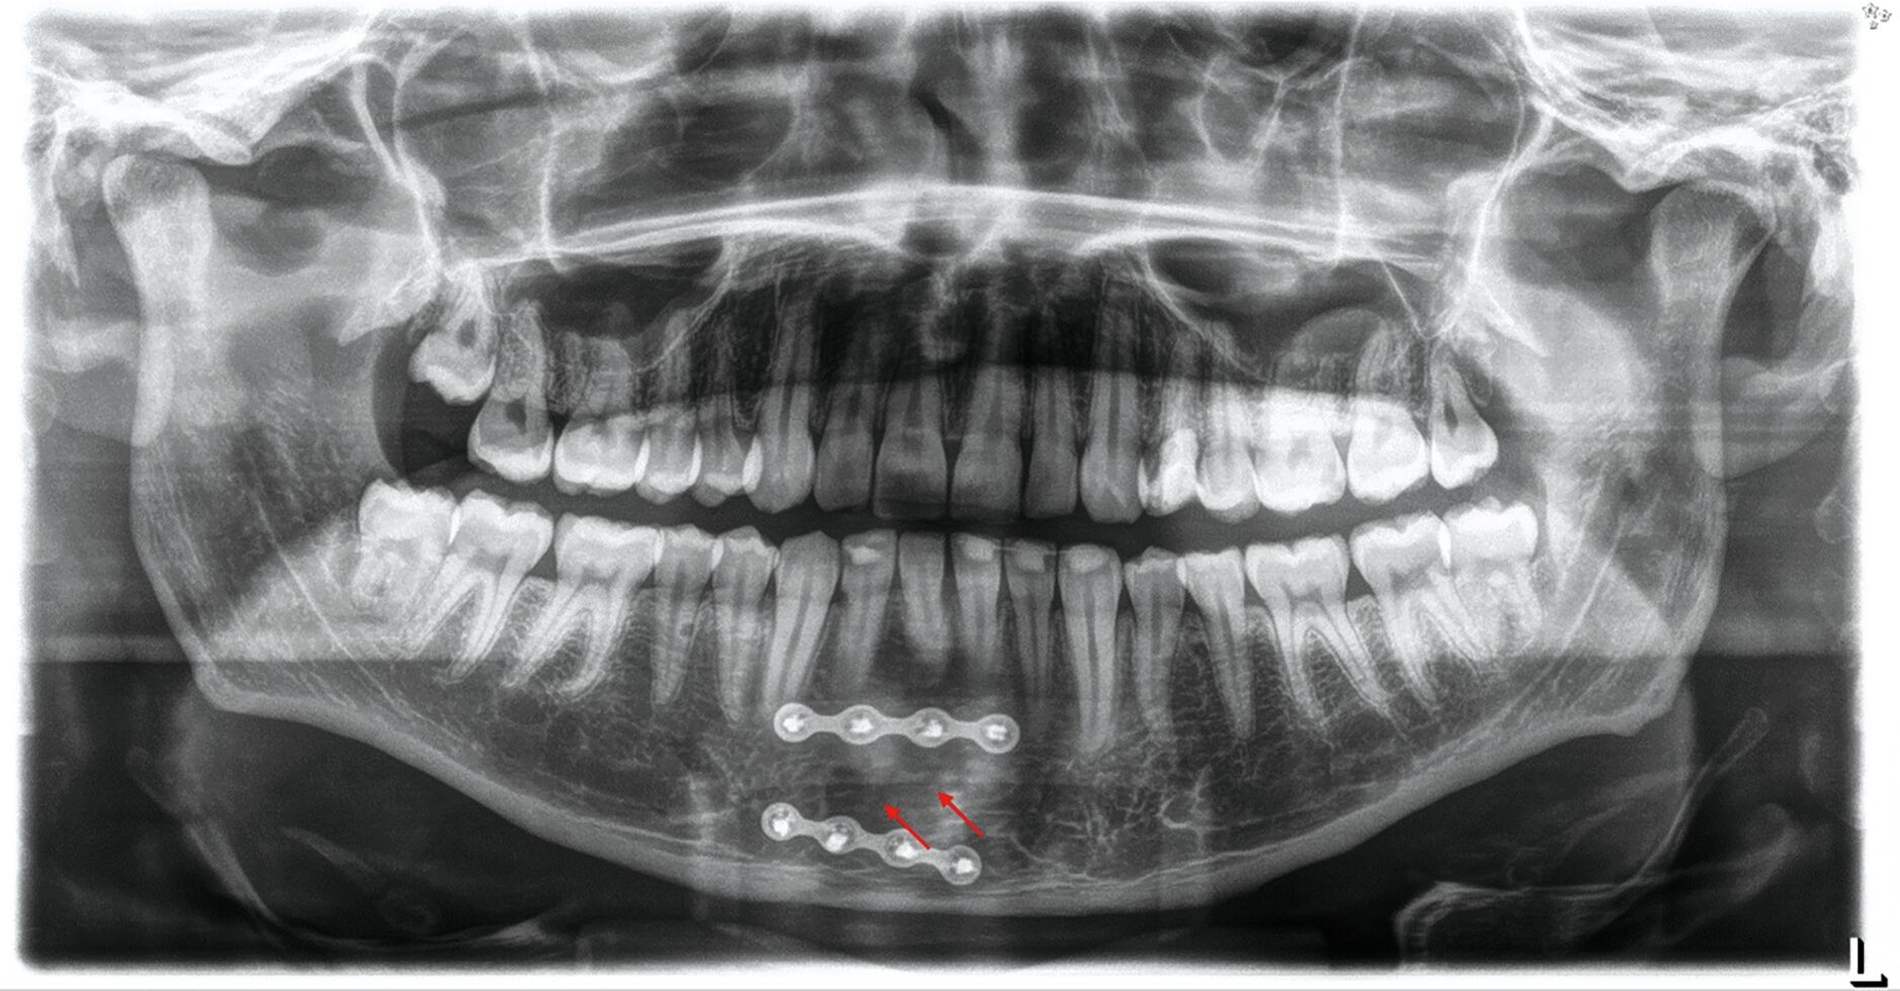

Zunächst wurden Einzelbildaufnahmen der Zähne 24, 26, 35, 33–43 angefertigt. Dabei fiel eine transluzente Frakturlinie ausgehend vom mesialen Parodontalspalt des 41 auf, die sich nach apikal-distal bis zum Apex des 42 darstellte (Abbildungen 3 und 4). Für einen radiologischen Überblick, mit dem auch eine Kiefergelenksfraktur ausgeschlossen werden kann, wurde eine Panoramaschichtaufnahme herangezogen (Abbildung 5). Darauf bildete sich eine unscharfe, C-förmige Transluzenz apikal der Zähne 31 und 41 ab. Eine genaue Beurteilung war nicht möglich, da der Bereich apikal der Unterkieferfront außerhalb der Bildebene lag. Die Processus coronoidei und condylares stellten sich beidseits unauffällig dar. Die Verdachtsdiagnose lautete: Unterkieferfraktur, unkomplizierte Kronenfrakturen an den Zähnen 26 und 35 sowie eine Längsfraktur an Zahn 24.

Laut dem radiologischen Befundbericht lag „eine nicht wesentlich dislozierte, paramediane Unterkieferfraktur rechts“ vor. Die Reposition und die Fixierung der Mandibula erfolgten am darauffolgenden Tag mithilfe von zwei Miniosteosyntheseplatten durch einen vestibulären Zugang in Intubationsnarkose. Die radiologische Kontrolle zwei Tage nach der operativen Versorgung ergab eine adäquate Stabilisierung der Fraktur durch die beiden Miniosteosyntheseplatten (Abbildung 7).